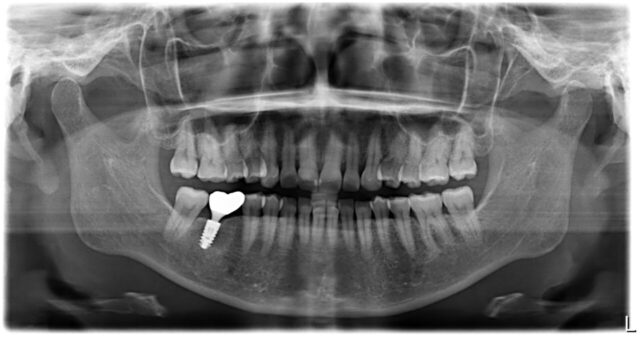

After

| 主訴 | 歯牙の破損 |

| 年齢 | 30代 |

| 性別 | 女性 |

| 治療期間・回数 | 5ヶ月 7回 |

| 治療方法 | インプラント治療 |

| デメリット・注意点 | きれいな歯を削らず長期間保存するため、インプラント治療を選択。 |

| 備考 | 治療前後ではなく、長期間安定しているインプラント症例の紹介です。 定期メンテナンスに来ていただき、12年3ヶ月の間、問題なくお過ごしいただいてます。 歯を削ることなく治療が完了しており、インプラントだけではなくお口全体がとてもきれいな状態を維持できています。 |